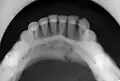

multiple mandible fractures of a patient in the right condyle (extracapsular/neck/not dislocated), right body (vertically unfavourable) and left coronoid process